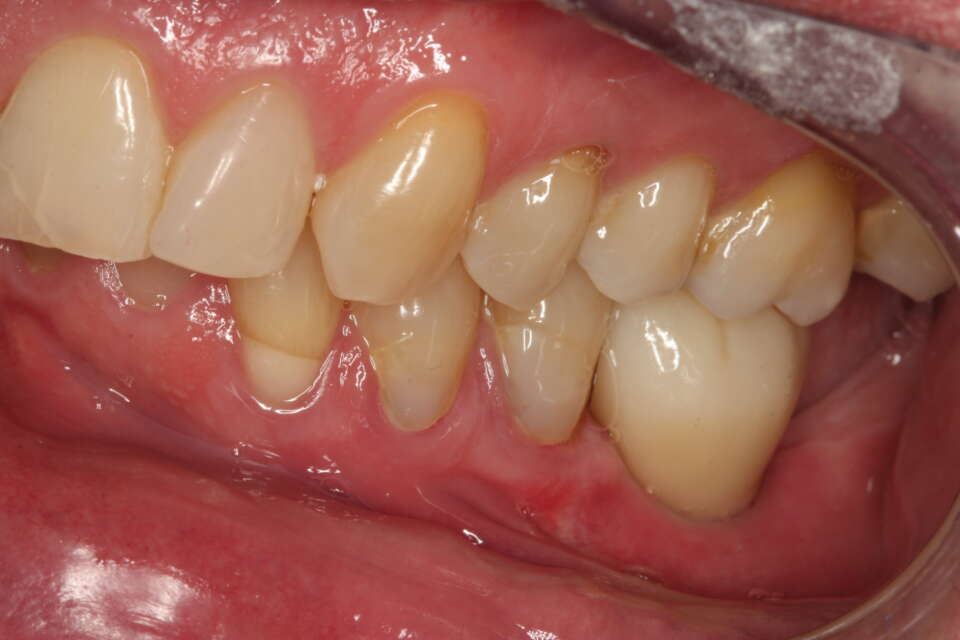

IMG 7533

Missing molars on the lower right side